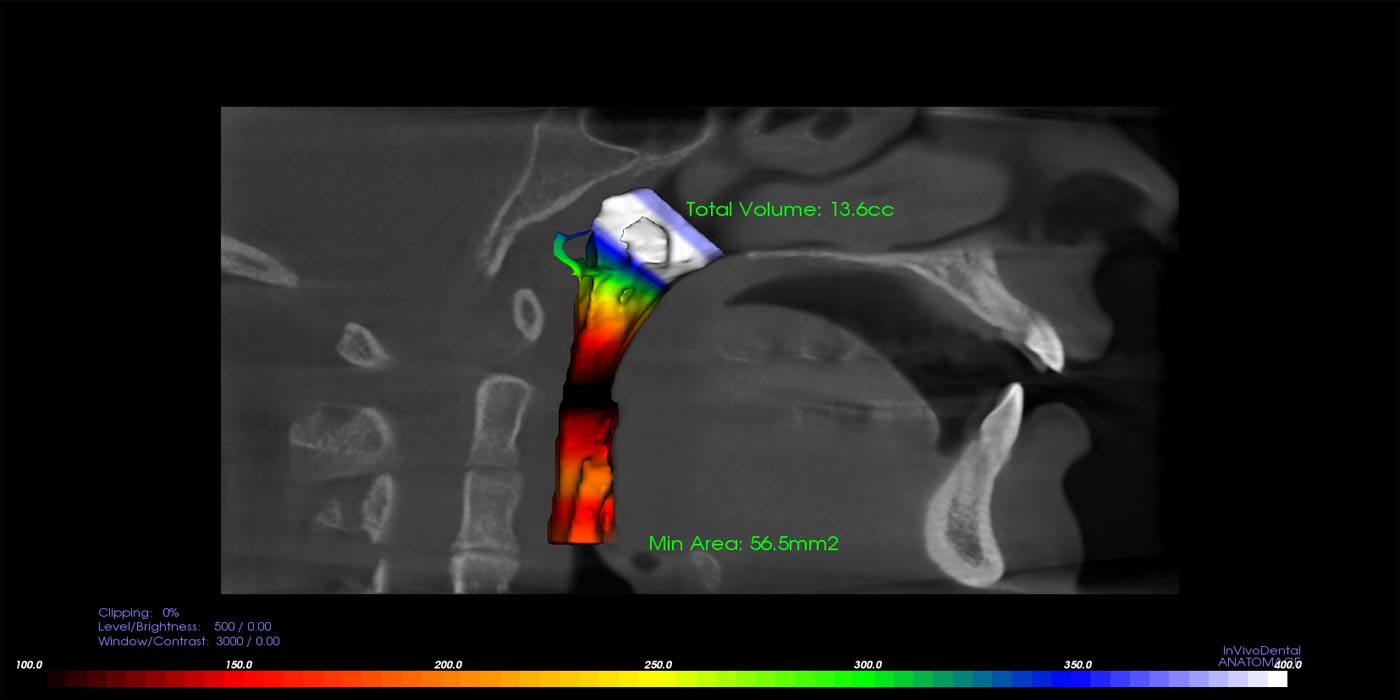

The upper airway is an extraordinarily complex anatomic region that may be affected by various disease states. The upper airway includes the nose, nasopharynx, oropharynx, hypopharynx, larynx, and trachea, and these structures may be involved by both focal and diffuse processes.

There are also many adjacent bony and soft tissue structures that are no less complex in their anatomic arrangement. Lesions in these regions can cause extrinsic compression resulting in a compromised airway. This scan will provide with detailed evaluation of the area and its diagnosis for various problems.